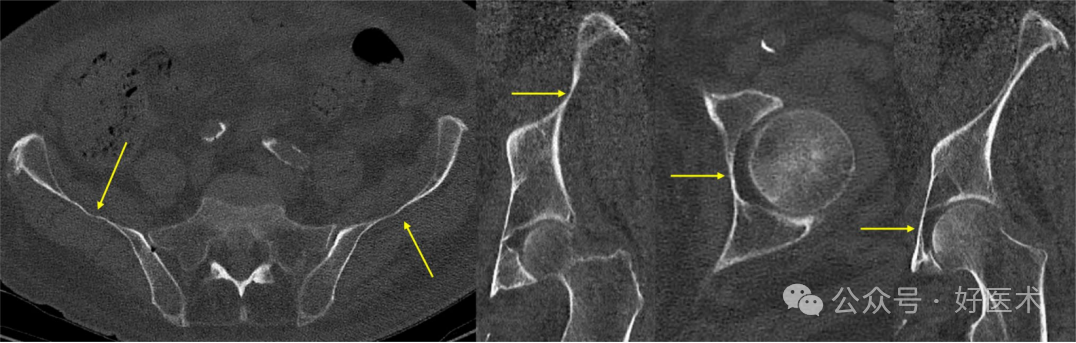

SAC 长度

Schildhauer定义了髋臼上缘通道(SAC)的整体路径和两个狭窄区域。在男性患者中,从骶骨后上棘(PSIS)到髂前下棘(AIIS)的平均长度为141.1毫米,而在女性患者中为128.7毫米。Pichler等人报告了类似的长度,为148毫米,而De Bondt等人发现性别之间没有显著差异(男性140毫米对比女性145毫米)。男性患者的 PIIS-AIIS 长度平均为 86.3 毫米,女性患者的 PIIS-AIIS 长度平均为 99.7 毫米。该通道内存在两个狭窄区域(图18)。

图18 髋臼上通道(SAC)在轴位CT扫描中的狭窄区域。

从后部开始到**个狭窄区域的距离,男性约为 3 厘米,女性约为 2.7 厘米。在上方通路(PSIS-AIIS),男性到第二个狭窄区域的距离为86.3mm,女性为84.1mm;在下方通路(PIIS-AIIS),男性为60.3mm,女性为52.8mm。因此,在这个通道中使用长螺钉进行三点稳定是可能的。髋臼上缘通道(SAC)的平均直径在男性中为8.3毫米,在女性中为6.2毫米。这种差异是由于女性的髂骨更呈S形。一种更大的替代髋臼上缘通道在男性中测量为11.3毫米,在女性中为9.9毫米。这种替代髋臼上缘通道的起始点更靠下(位于髂前下棘AIIS的下方),出口点位于骶骨后上棘(PSIS)的前方,导致其角度更偏向头侧(图19)。这种替代髋臼上缘通道(SAC)存在进入关节内的风险,因为髋关节囊附着点可延伸至髋臼缘上方1.6厘米处。